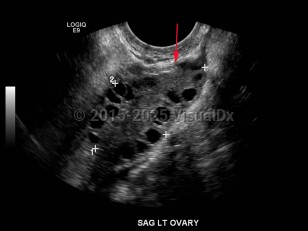

Although the exact etiology of the syndrome is unclear, women with PCOS have increased luteinizing hormone (LH) and low-to-normal follicle stimulating hormone (FSH). This is either a result of some inherent fault of hypothalamic-pituitary function, improper hypothalamic-pituitary-ovarian feedback mechanisms, or both. The increased LH stimulates an overproduction of androgens in the ovary; while some androgen will be converted to estrogen by aromatase, the overall hormonal milieu within the ovary is androgen dominant. This leads to an environment in which none of the smaller, immature ovarian follicles can arise as a mature dominant follicle. As such, the ovary takes on a polycystic appearance, with an overabundance of small follicles causing a cystic architecture on ultrasound.